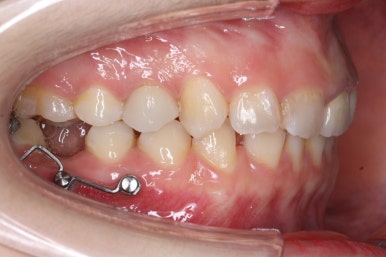

치료 과정을 순차적으로 보겠습니다.

임플란트를 식립하기 위한 공간이 서서히 확보가 되어 가는 것이 보입니다. 어금니만한 사이즈로 공간이 확보가 되면 식립이 이뤄지죠.

측면에서 본 모습입니다.

자리가 점점 넓어지는 것이 보입니다.